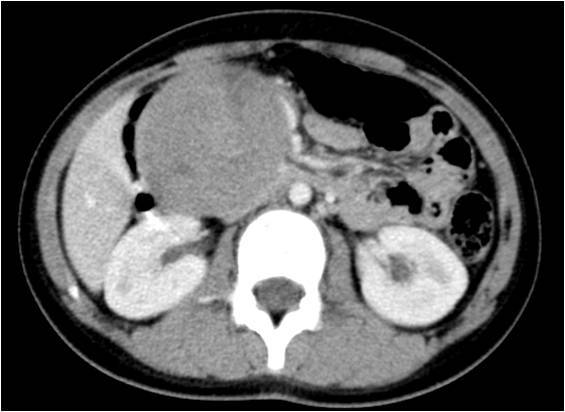

患者张**,女,11岁8个月,因“上腹部胀痛不适3个月”就诊当地医院,腹部ct提示胰头巨大肿瘤、压迫周围血管并导致肠系膜上静脉狭窄变型。为手术治疗转诊我院!

术前ct:

患者术前诊断考虑“胰头巨大实性假乳头状瘤”,治疗需行胰十二指肠切除术!但该手术风险大,术后并发症发生率高,且患者肿瘤巨大、压迫血管致手术难度增加;患者年龄较小,围手术期治疗棘手!为此,我们做了充份的预案!于2019年7月24日成功进行了保留幽门的胰十二指肠切除术(保留幽门可最大程度保留营养吸收,为患者以后生长发育提供条件)。